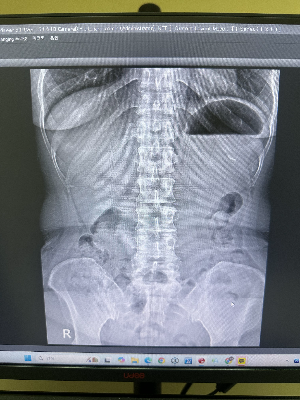

2. 천장을 보고 누운 '정면 사진(AP)'이 알려주는 단서들

환자분이 천장을 보고 반듯하게 누웠을 때 찍는 정면 사진(Antero-Posterior view)은 주로 허리뼈의 '좌우 균형'을 확인하는 데 핵심적인 역할을 합니다.

① 척추측만증 (Scoliosis) 확인

정상적인 사람의 척추를 정면에서 바라보면 일직선(I자)으로 곧게 뻗어 있어야 합니다. 하지만 정면 사진을 찍었을 때 척추가 S자나 C자 형태로 좌우로 심하게 휘어져 있다면 '척추측만증'을 의심할 수 있습니다. 이는 측면 사진에서는 절대 발견할 수 없는 정면 사진만의 고유한 역할입니다.

② 골반의 틀어짐과 다리 길이 차이

허리 통증의 원인이 척추 자체의 문제가 아니라, 골반이 심하게 틀어져 있거나 양쪽 다리 길이에 차이가 나서 발생하는 경우도 많습니다. 정면에서 넓게 촬영된 요추 X-ray를 보면 양쪽 골반뼈(장골능)의 높낮이를 직관적으로 비교할 수 있어 체형 불균형을 진단하는 데 큰 도움이 됩니다.

③ 척추뼈의 미세한 골절 (횡돌기 골절 등)

교통사고나 낙상 등 강한 외부 충격을 받았을 때, 척추뼈 양옆으로 튀어나온 얇은 뼈(횡돌기)가 부러지는 경우가 있습니다. 이 부위는 측면 사진에서는 다른 두꺼운 뼈들에 가려져 보이지 않기 때문에 반드시 정면 사진을 통해 꼼꼼하게 골절 여부를 확인해야 합니다.